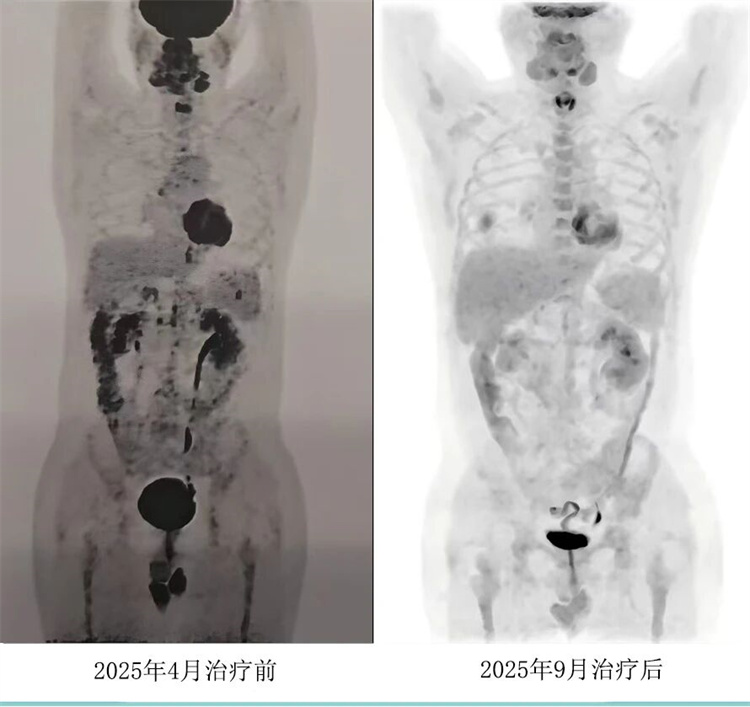

病例汇报环节由我院淋巴瘤科张薇医生带来了三例精彩纷呈的难治复发弥漫大B淋巴瘤CAR-T治疗的病例。

病例过程跌宕起伏,从桥接治疗到靶点的选择,并发症的处理都极具代表性。张医生详尽分享了患者在治疗过程中的挑战、决策依据以及CAR-T细胞治疗后的惊人缓解与转归,充分展示了CAR-T技术为晚期患者带来的突破性生存希望。